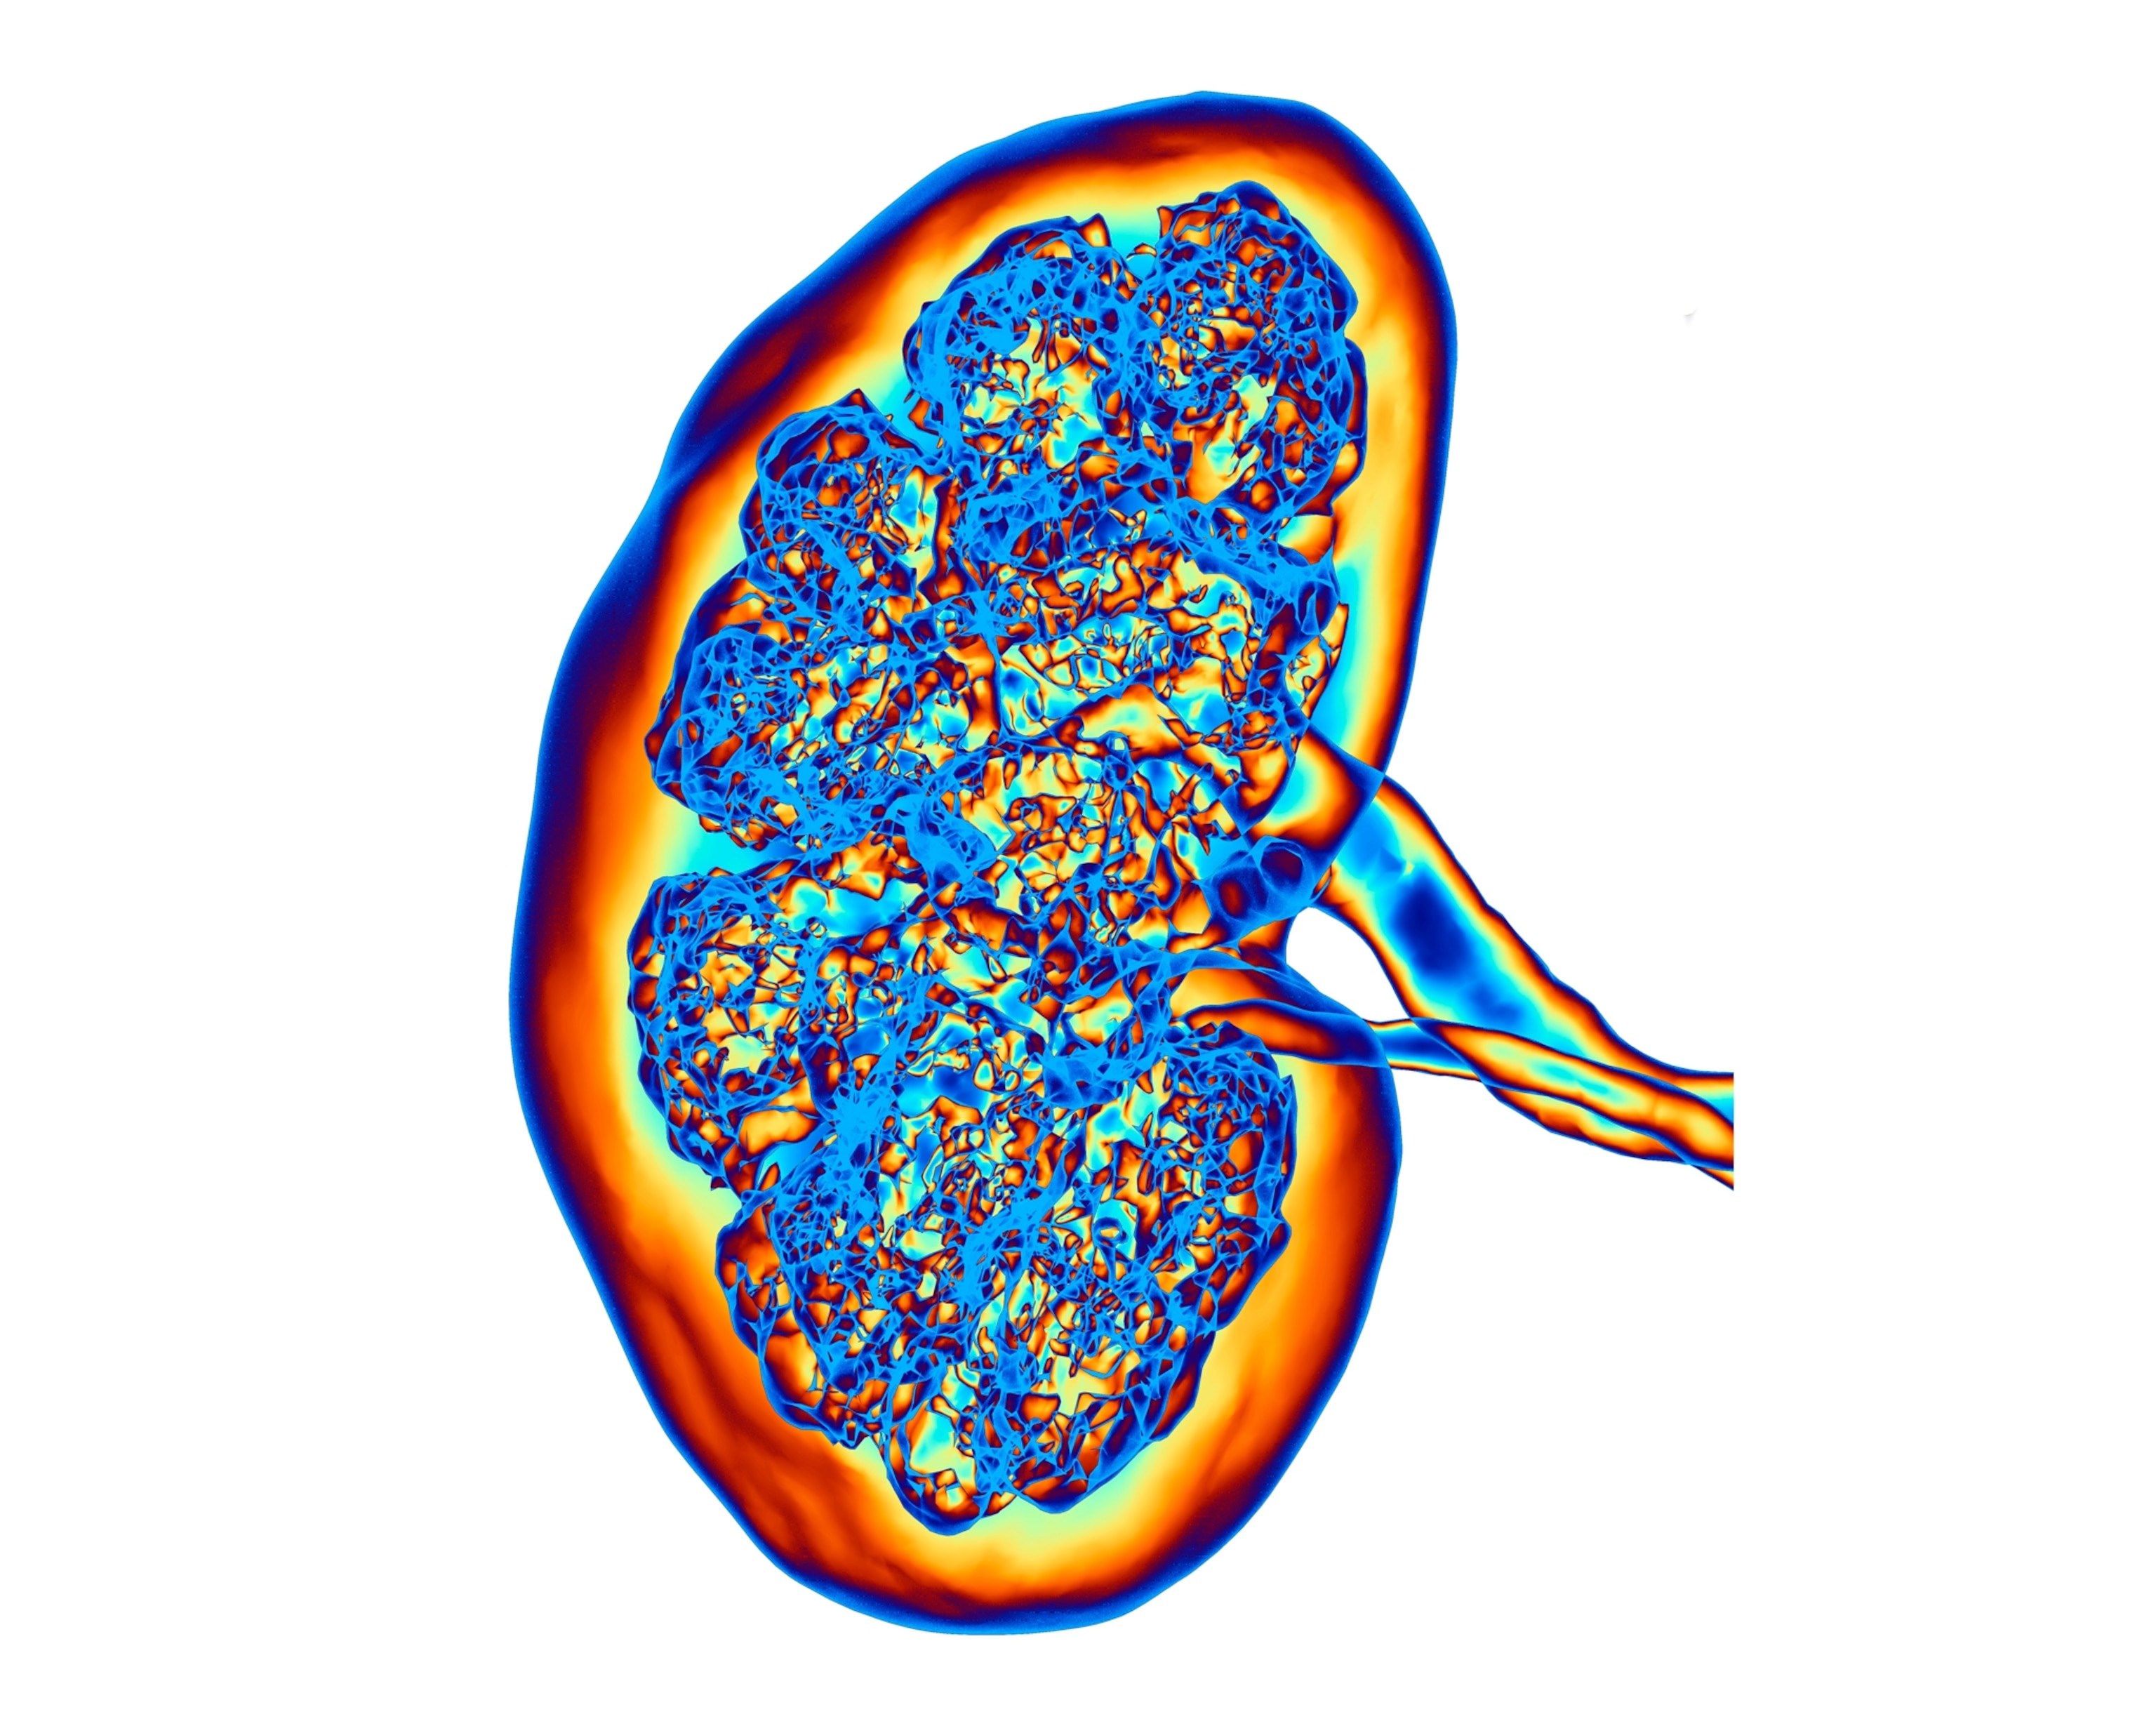

The kidneys are responsible for filtering our blood, removing toxins and keeping its beneficial compounds. They also play an important role in regulating the amount of fluid in our bodies, ensuring that enough blood cells are made, and controlling blood pressure.

“The kidneys are a bunch of small blood vessels that form these microscopic filters,” Parikh says. The problem, Parikh says, is that these filters can’t be replaced, which means that “the filters you are born with have to last a lifetime.” If these blood vessels get damaged, then the kidneys lose their ability to function properly.